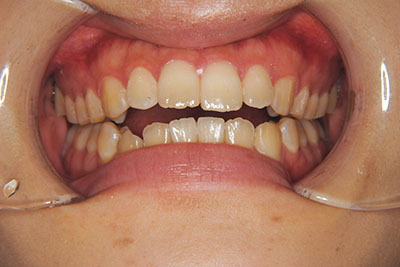

おとなの方でも矯正治療をあきらめないでください!

矯正歯科治療は子供の頃だけしかできない……

子供の頃に比べ大人になったら治療期間がすごく長い……

というようなイメージをお持ちではありませんか?

子供の頃に矯正治療を行う方が治療期間が短く済むというのは、確かですが、矯正治療は患者様の意識も重要です。

いくら歯が動き易くとも、本人がやる気でなければ効果は出ませんし、むし歯発生のリスクも高まります。おとなの方は顎の成長が終わっているため、治療の計画が立てやすいとも言えます。「もう大人だから…」とあきらめず、一度ご相談ください。